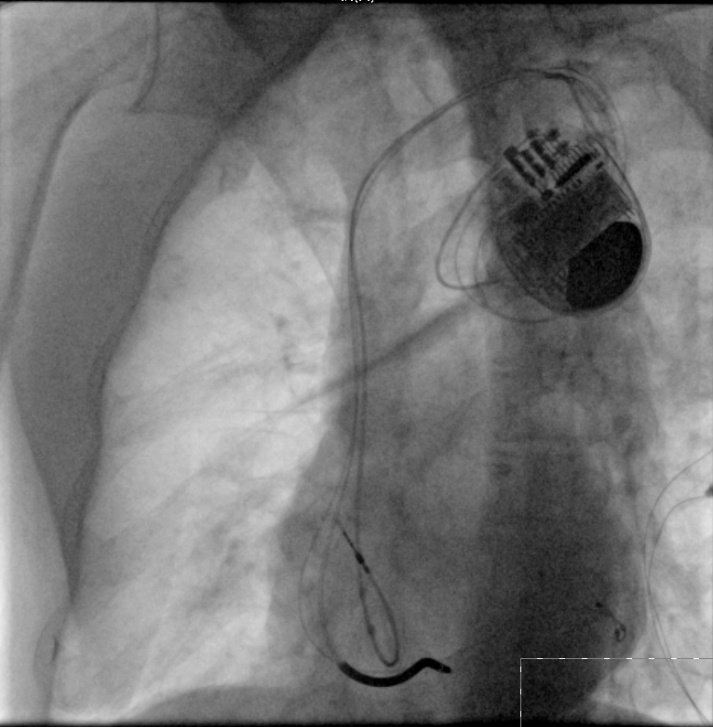

90岁的刘大爷,因为心衰反复出现呼吸困难及双下肢水肿,心脏彩超提示左心室舒张末期内径达62mm(正常男性小于55mm),左室射血分数仅27%,心电图提示窦性心律,完全性左束支传导阻滞,单纯药物治疗后无效。在泸州市中医院心衰中心接受带除颤功能的三腔起搏器植入术及规范的药物治疗并定期随访,现心脏彩超提示左心室舒张末期内径恢复到57mm,左室射血分数恢复到45%。目前,刘大爷散步、养花、做家务已经没有了呼吸困难,也没有再出现双下肢水肿及腹胀,也不用再频繁住院,提高了生活质量。

带除颤功能的三腔起搏器植入术(CRTD)